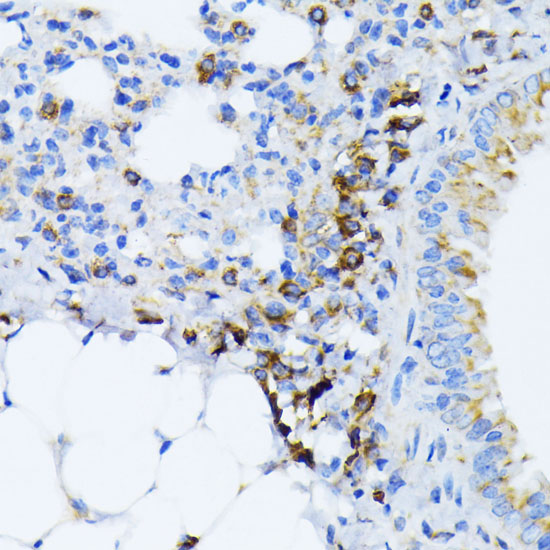

Immunohistochemistry of paraffin-embedded mouse lung using BiP/GRP78 antibody.